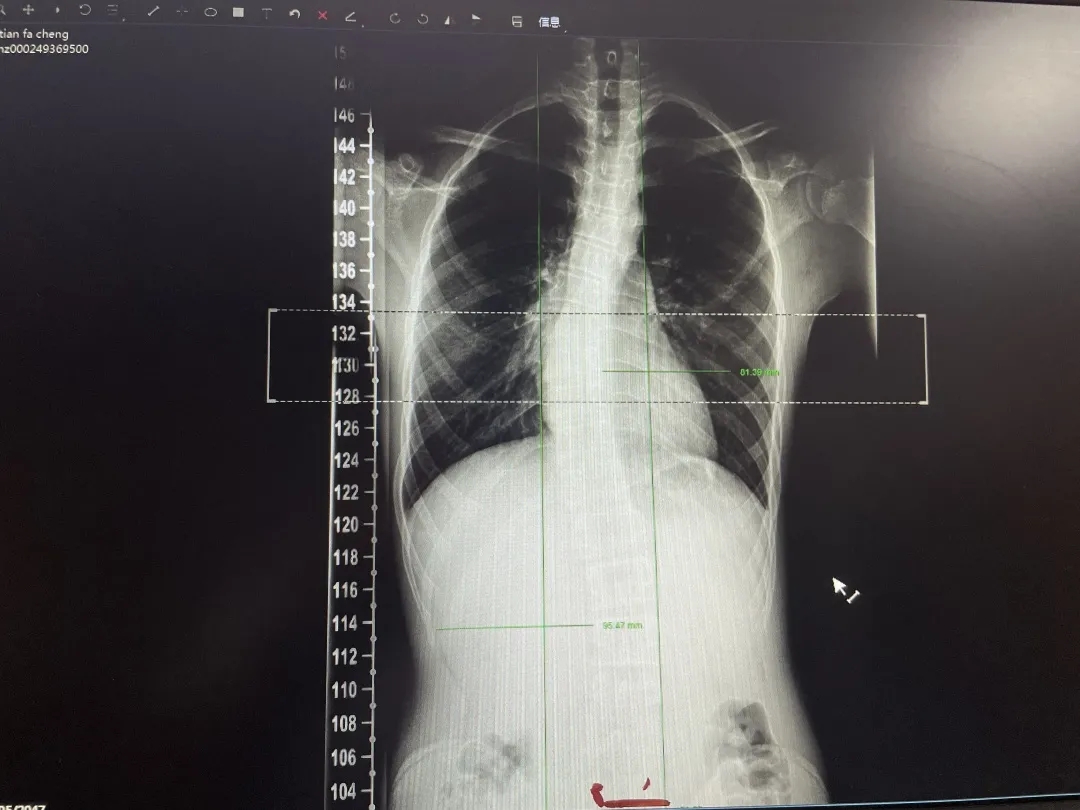

放松与整复完成后,主管治疗师刘智为小明制定了一份训练计划,通过运动训练的方式强化弱势机群,增强本体感觉,进而恢复肌肉功能。为解决脊柱旋转问题,还给小明进行脊柱活动度训练和矫正训练,同时进行腹式呼吸训练和核心力量训练,增强小明的核心稳定。小明的脊柱侧弯得到了明显改善,不良体态基本消失,小明变得更加阳光与自信!一个疗程结束后,小明将继续治疗,争取得到更大的进步。

康复治疗后X光检查